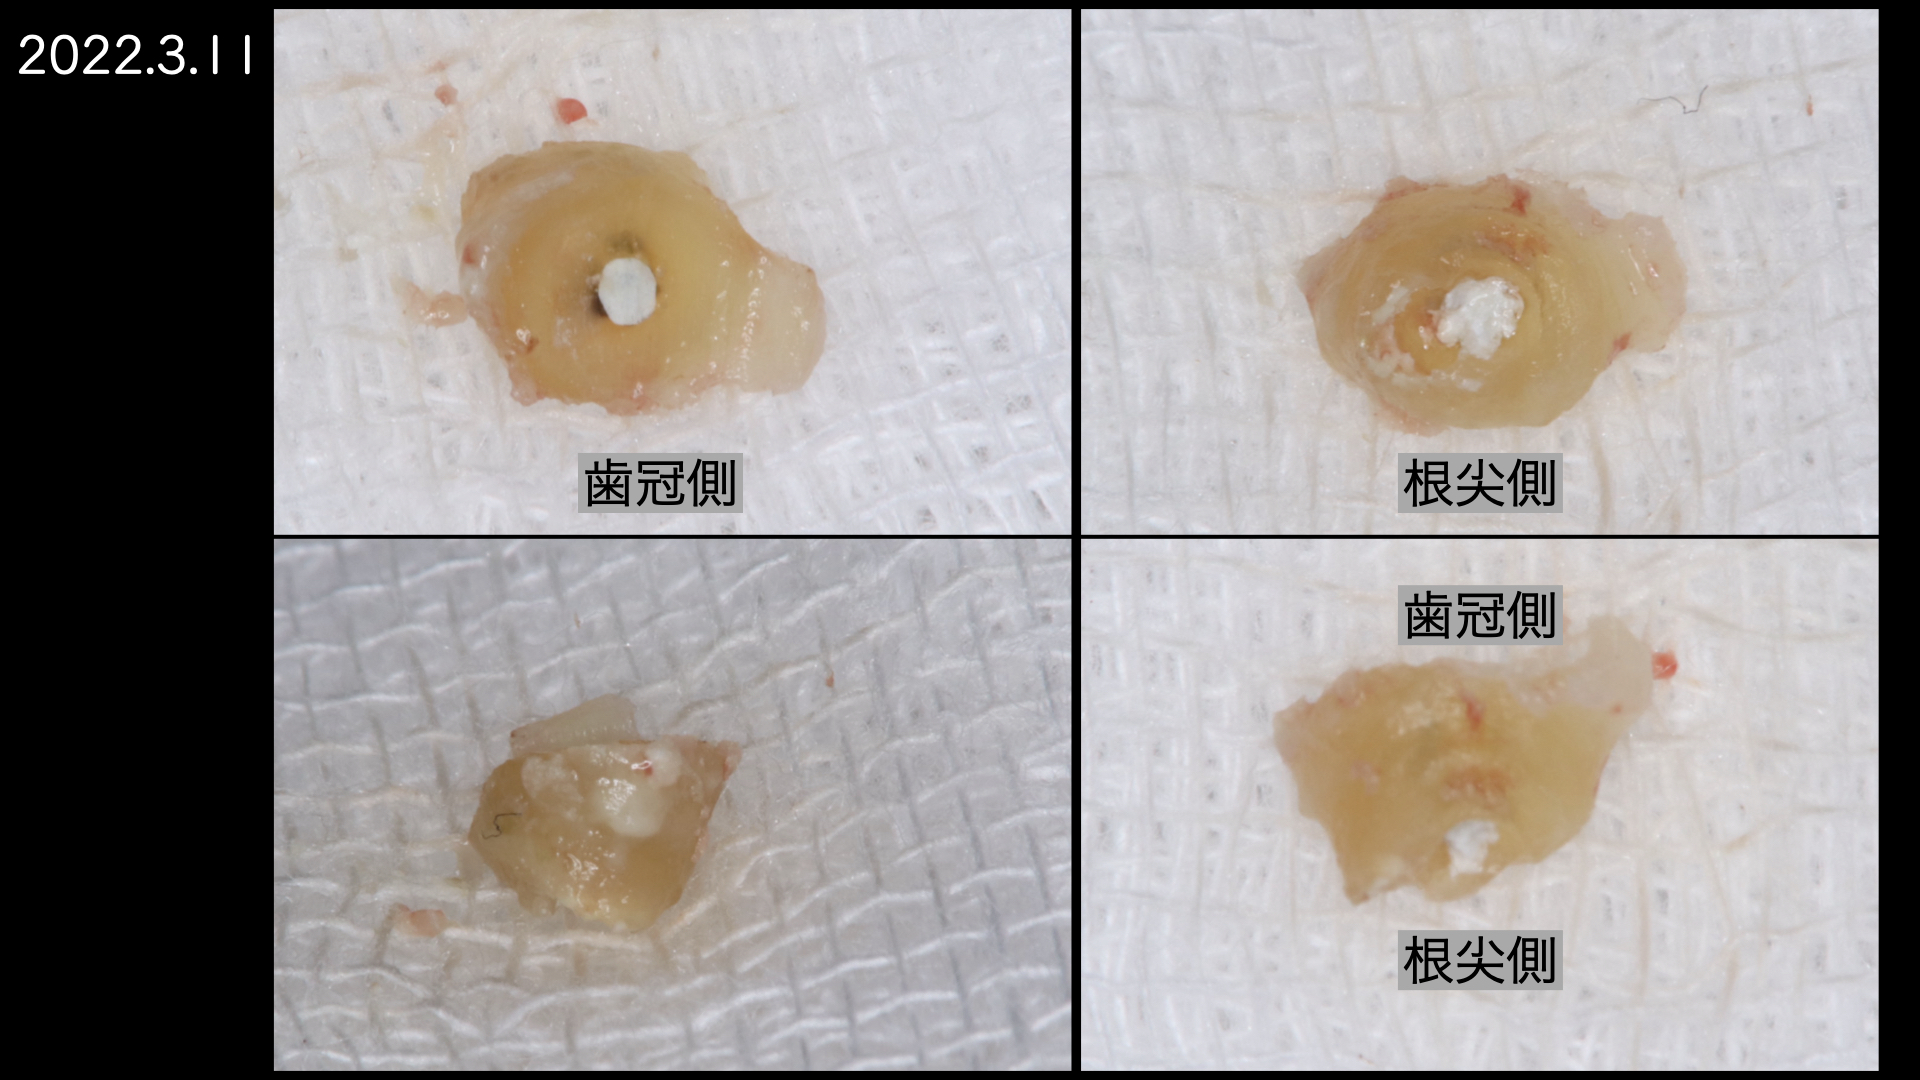

切断した歯根です。表面が粗造になっており、感染が根尖孔外にあったことを認めます。